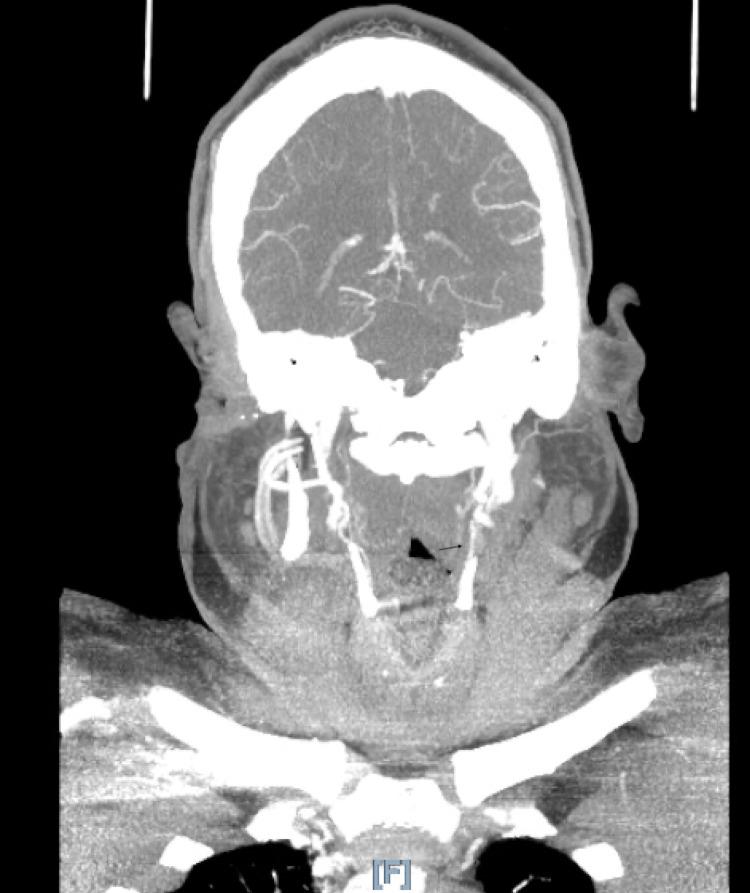

Bilateral internal carotid artery occlusion (BICAO) is a rare disease leading to serious cerebrovascular disease and complications including recurrent ischemic stroke or death. There are very few cases reported on BICAO, especially among young adults. The clinical presentation can range from asymptomatic to fatal ischemic stroke depending upon the presence of adequate collateral blood flow. Here we report a case of BICAO in a 31-year-old female who presented with intermittent left-sided hemiparesis for one day and was subsequently found to have complete occlusion of the bilateral intracranial internal carotid arteries on CT angiography (CTA). Magnetic resonance imaging (MRI) brain showed sub-acute right middle cerebral artery (MCA), acute left middle cerebral artery, and anterior cerebral artery infarcts (ACA). Being outside the window for thrombolysis, she was successfully treated with balloon angioplasty of the left internal carotid artery (ICA) and started on dual antiplatelet therapy. The case illustrates the importance of evaluating for cerebrovascular disease when someone presents with stroke-like symptoms even in the young adult population, as prompt treatment can be lifesaving.

双侧颈内动脉闭塞(BICAO)是一种罕见疾病,可导致严重的脑血管疾病及包括复发性缺血性卒中或死亡在内的并发症。关于BICAO的病例报道极少,尤其是在年轻成年人中。临床表现因是否存在充足的侧支血流而异,从无症状到致命性缺血性卒中不等。在此,我们报告一例31岁女性的BICAO病例,该患者出现间歇性左侧偏瘫1天,随后在CT血管造影(CTA)检查中发现双侧颅内颈内动脉完全闭塞。脑部磁共振成像(MRI)显示右大脑中动脉(MCA)亚急性梗死、左大脑中动脉急性梗死以及大脑前动脉(ACA)梗死。由于已过溶栓时间窗,她接受了左侧颈内动脉(ICA)球囊血管成形术治疗并成功治愈,随后开始双联抗血小板治疗。该病例表明,即使在年轻成年人群中,当有人出现类似卒中症状时,评估脑血管疾病非常重要,因为及时治疗可挽救生命。